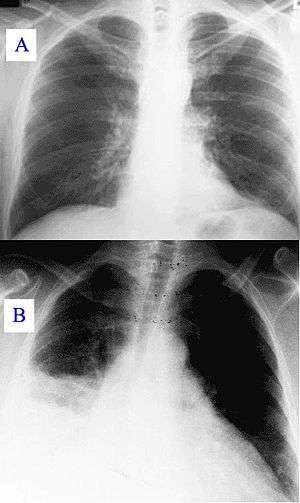

Silhouette sign

In radiology, the silhouette sign refers to the loss of normal borders between thoracic structures.[1] It is usually caused by an intrathoracic radiopaque mass that touches the border of the heart or aorta.[2] In other words, it is difficult to make out the borders of a particular structure - normal or otherwise - because it is next to another dense structure, both of which will appear white on a standard X-ray.[3] It may occur, for example, in right middle lobe syndrome, where the right heart margin is obscured, and in right lower lobe pneumonia, where the border of the diaphragm on the right side is obscured, while the right heart margin remains distinct.[2] Silhouette sign is very useful in localizing lung lesions as all structures forming cardiac silhouette are in contact with a specific portion of the lung.